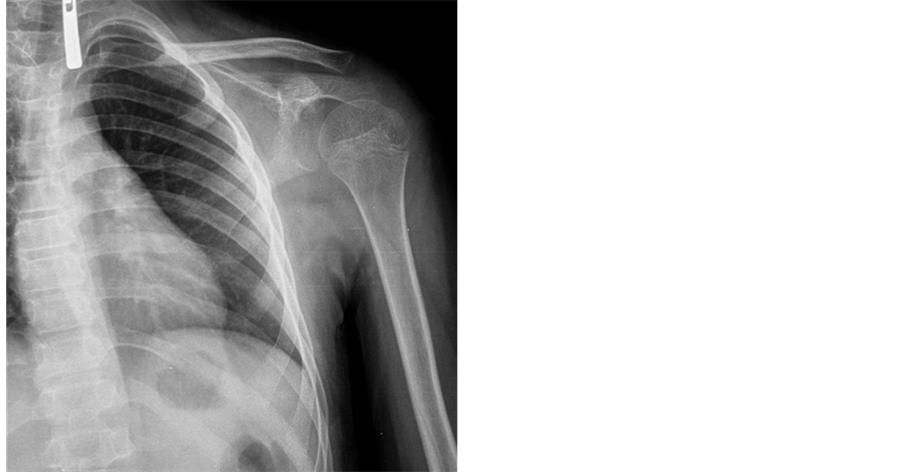

An 11-year-old male presented to our hospital following a fall onto the shoulder. Initially, direct radiographs showed no fractures. He also exhibited no neurovascular deficits. However, he reported intense pain localised to the anterior aspect of his shoulder. Computed tomography showed an isolated fracture of the base of the coracoid (Figure 3 and Figure 4). The patient was treated conservatively using a broad arm sling with analgesics for 3 weeks followed by active shoulder exercises. At 3 months, he was pain-free with a full range of motion.

Figure 3. Anteroposterior roentgenograph of case 2. Fracture clear image in this roentgenograph is not available.